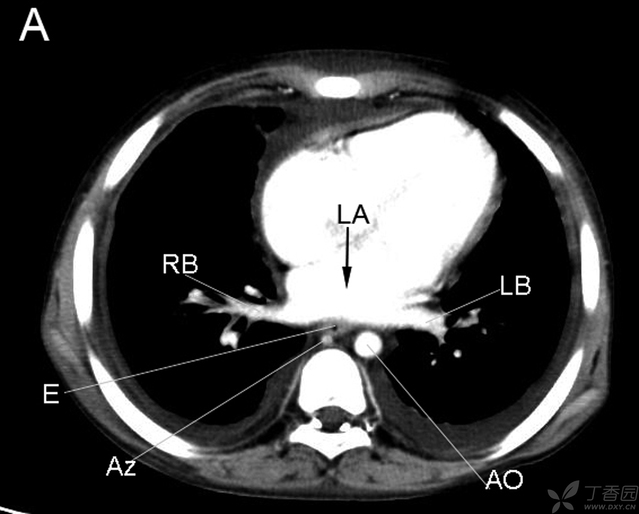

RB右支气管 LA左房 LB左支气管 E食管 AZ奇静脉 AO主动脉

Lung肺 v脊柱 Tr气管 LPB左主支气管 RPB右主支气管

RA右房 RV右室 LA左房 LV左室